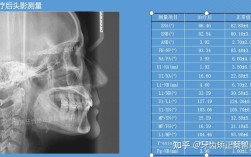

解答:实际上无需区分这两个概念,因为它们指向同一种治疗——即通过专业手段矫正牙齿和颌骨的异常,是否需要接受这类治疗,取决于是否存在错畸形(如牙齿拥挤、稀疏、深覆合、深覆盖、反颌、开颌、面部不对称等),这些问题会影响咀嚼功能、面部美观甚至心理健康,建议到正规口腔医院的正畸科就诊,医生会通过临床检查(口内检查、面部观察)、影像学检查(X光片、CBCT)等明确诊断,判断是单纯的牙齿排列问题,还是伴有颌骨发育异常,并制定个性化的治疗方案(可能包括传统矫治、隐形矫治、功能矫治或联合正颌手术),患者只需关注“是否存在牙颌问题”以及“如何解决”,无需纠结于“正畸”或“牙颌正畸”的术语差异。